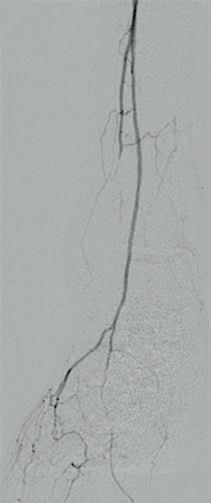

Figure 1: Diffuse calcified occlusive disease on pre-procedural arteriogram

a) Anterior tibial (AT) artery b) Dorsalis pedis (DP) artery

Figure 2: Shockwave Javelin in therapy a) In the AT b) In the DP

Figure

3: Definitive therapy, AT and DP treated with a 2.5x150mm angioplasty balloon a) Completion angiogram of AT b) Completion angiogram of DP

Views on optimal access vary. While Kim prefers a contralateral approach for precision to traverse tough lesions, both Foley and Tran err toward an antegrade access.

“If there is no inflow disease, no disease in the common femoral artery, no disease in the femoropopliteal region that I think is significant, so that, going in, there is going to be a high likelihood I’m doing a below-knee or a tibial or even a pedal artery intervention, I approach all of those cases from an antegrade approach,” says Foley. “And I don’t have any hesitation to do that because I believe that, with an antegrade approach for below the knee, especially for calcified lesions, really stenotic or at least occlusive lesions, you have a much better chance of getting across them. You get much better pushability and tactile feedback than you would if you were going up and over from a contralateral approach.